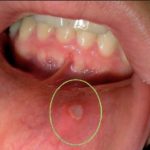

Важно понимать, насколько опасен ротовой сепсис – фото можно посмотреть в интернете, чтобы представить, насколько неэстетичная картина будет наблюдаться при заражении и попытках вылечиться самостоятельно. Необходимо срочно обратиться к врачу, если пораженная область стала болеть, в ней ощущается пульсация, возникает отек. Дополнительными симптомами считают высокую температуру, слабость, головные или сердечные боли.